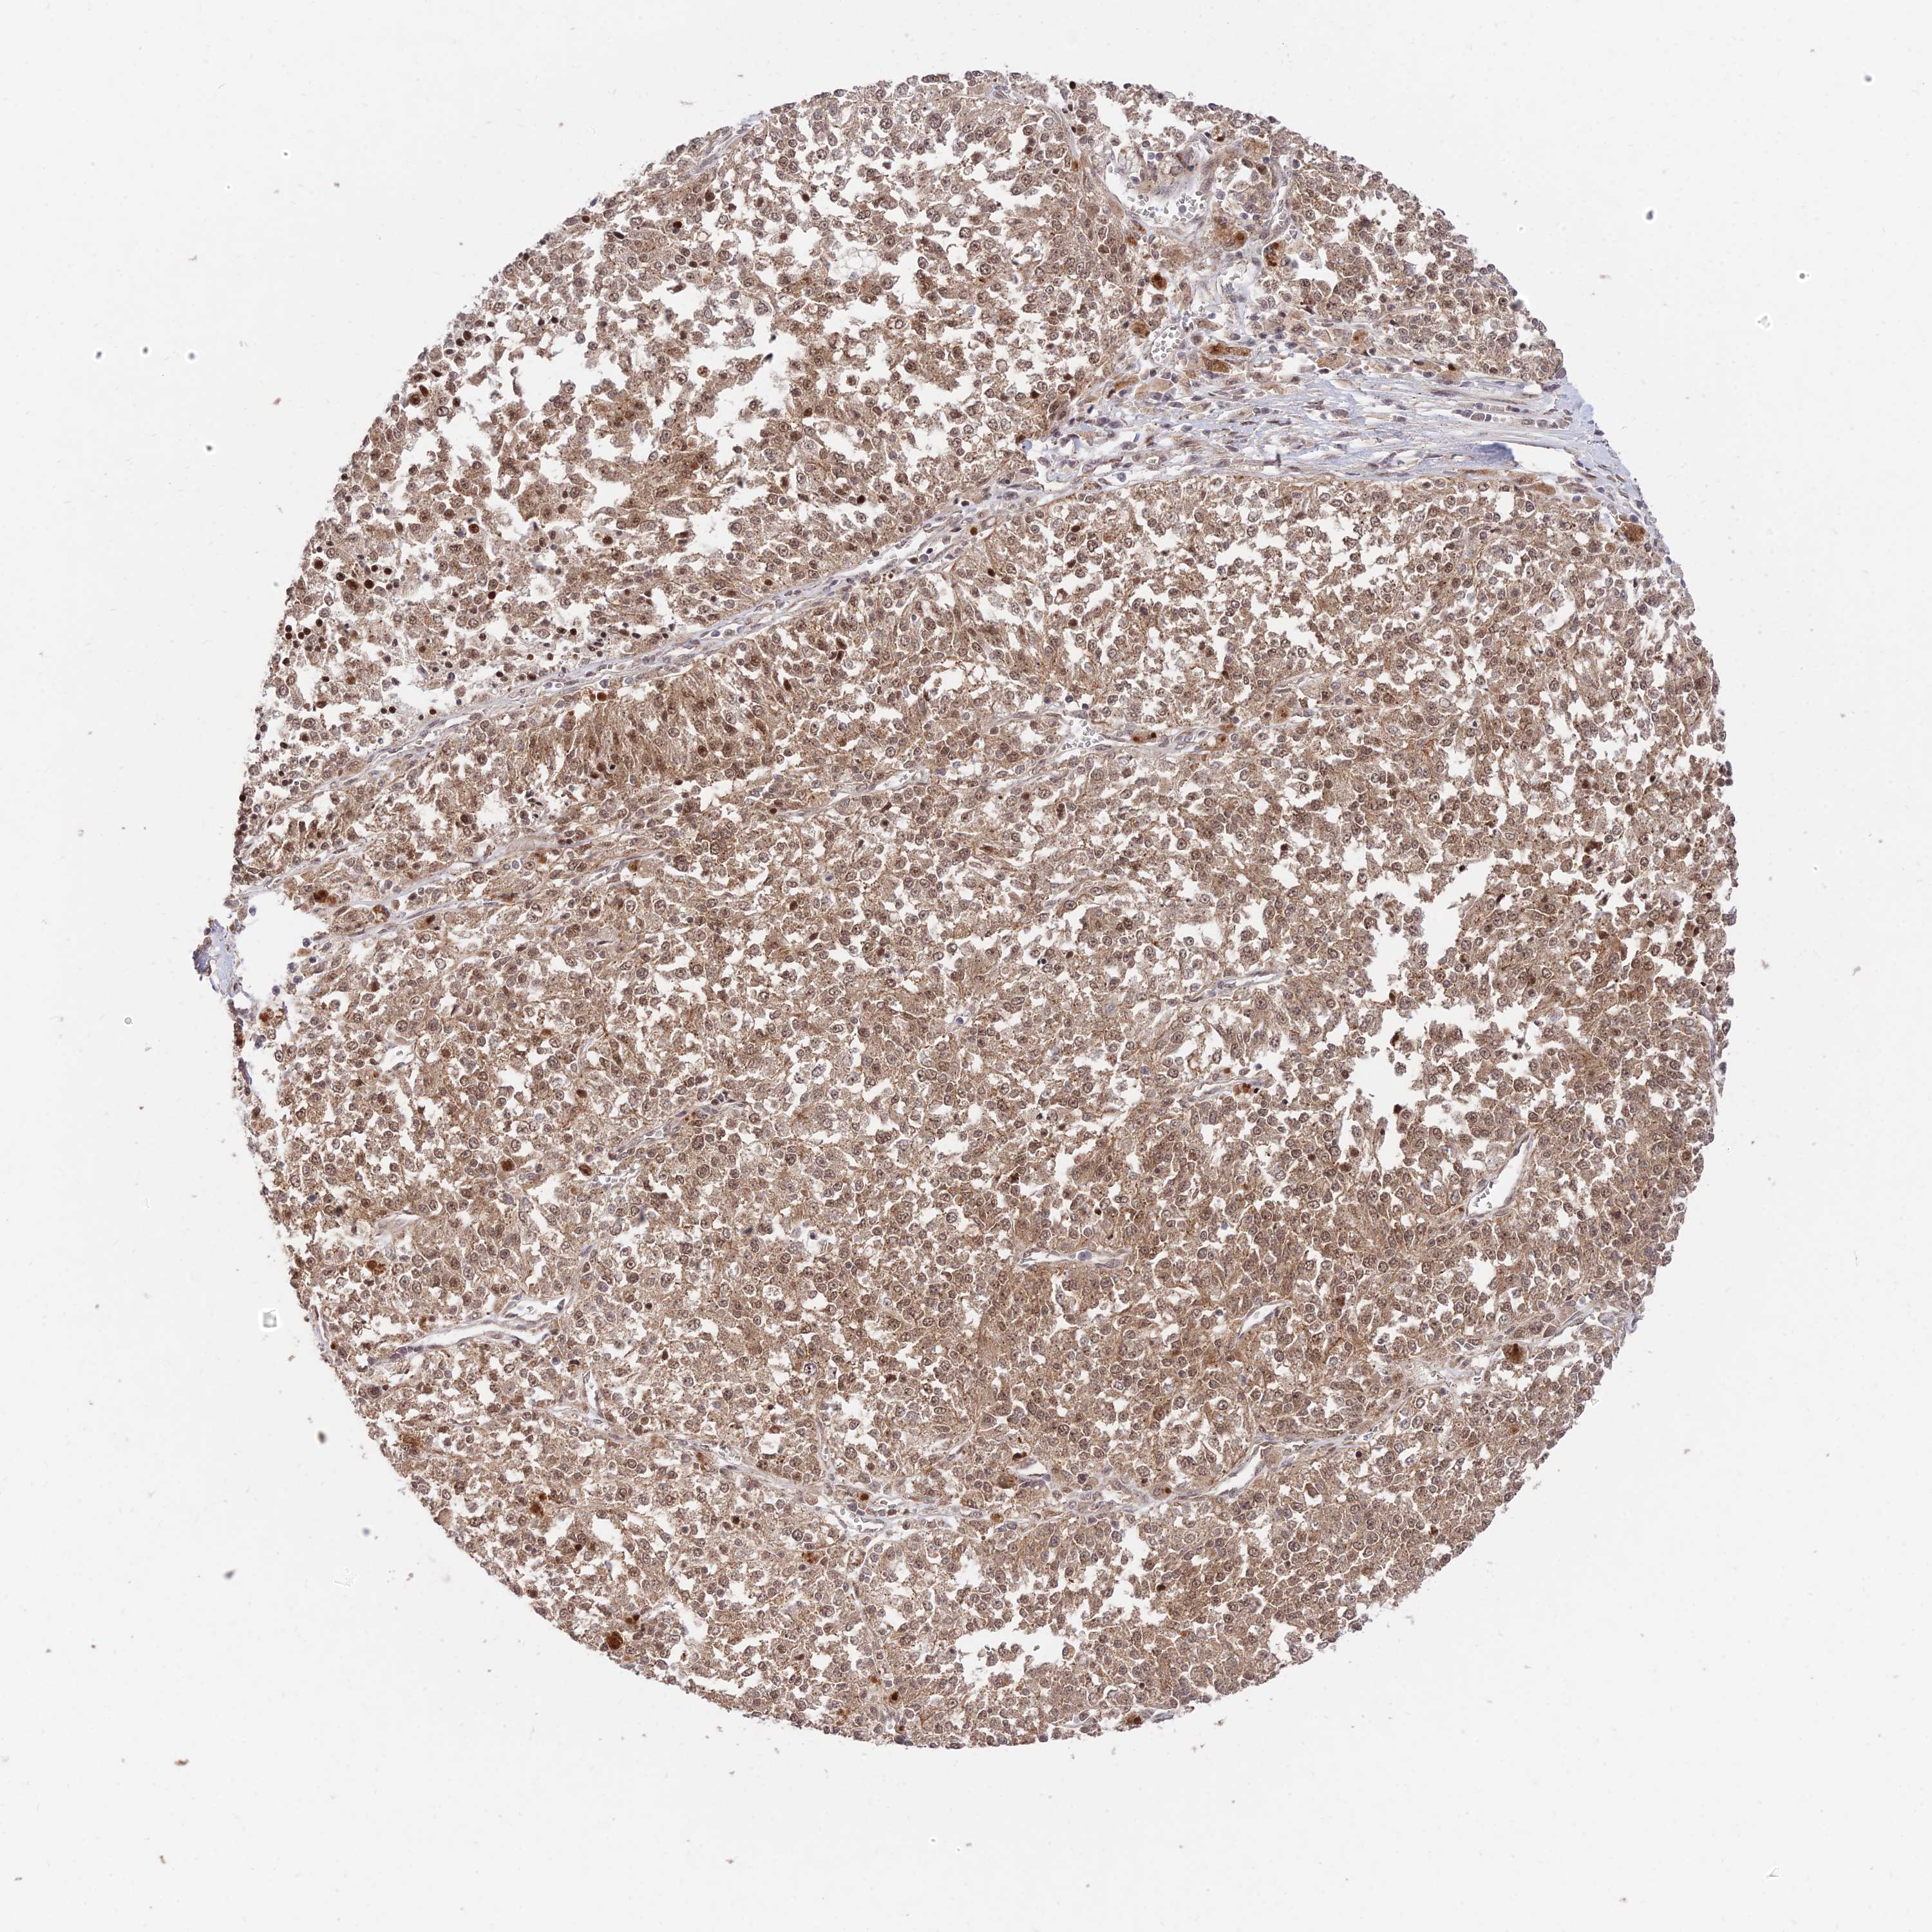

MELANOMA - Protein expressioni

A mouse-over function shows sample information and annotation data. Click on an image to view it in a full screen mode. Samples can be filtered based on level of antibody staining by selecting one or several of the following categories: high, medium, low and not detected. The assay and annotation is described here.

Note that samples used for immunohistochemistry by the Human Protein Atlas do not correspond to samples in the TCGA dataset.

Antibody stainingi

Antibody staining in the annotated cell types in the current human tissue is reported as not detected, low, medium, or high, based on conventional immunohistochemistry profiling in selected tissues. This score is based on the combination of the staining intensity and fraction of stained cells.

Each image is clickable and will lead to virtual microscopy that enables deeper exploration of all samples and also displays staining intensity scores, fraction scores and subcellular localization as well as patient and tissue information for each sample.

Antibody HPA044760

Staining

High

Medium

Low

Not detected

Intensity

Strong

Moderate

Weak

Negative

Quantity

>75%

75%-25%

<25%

None

Location

Nuclear

Cytoplasmic/membranous

Cytoplasmic/membranous,nuclear

Malignant melanoma, NOS

Malignant melanoma, Metastatic site